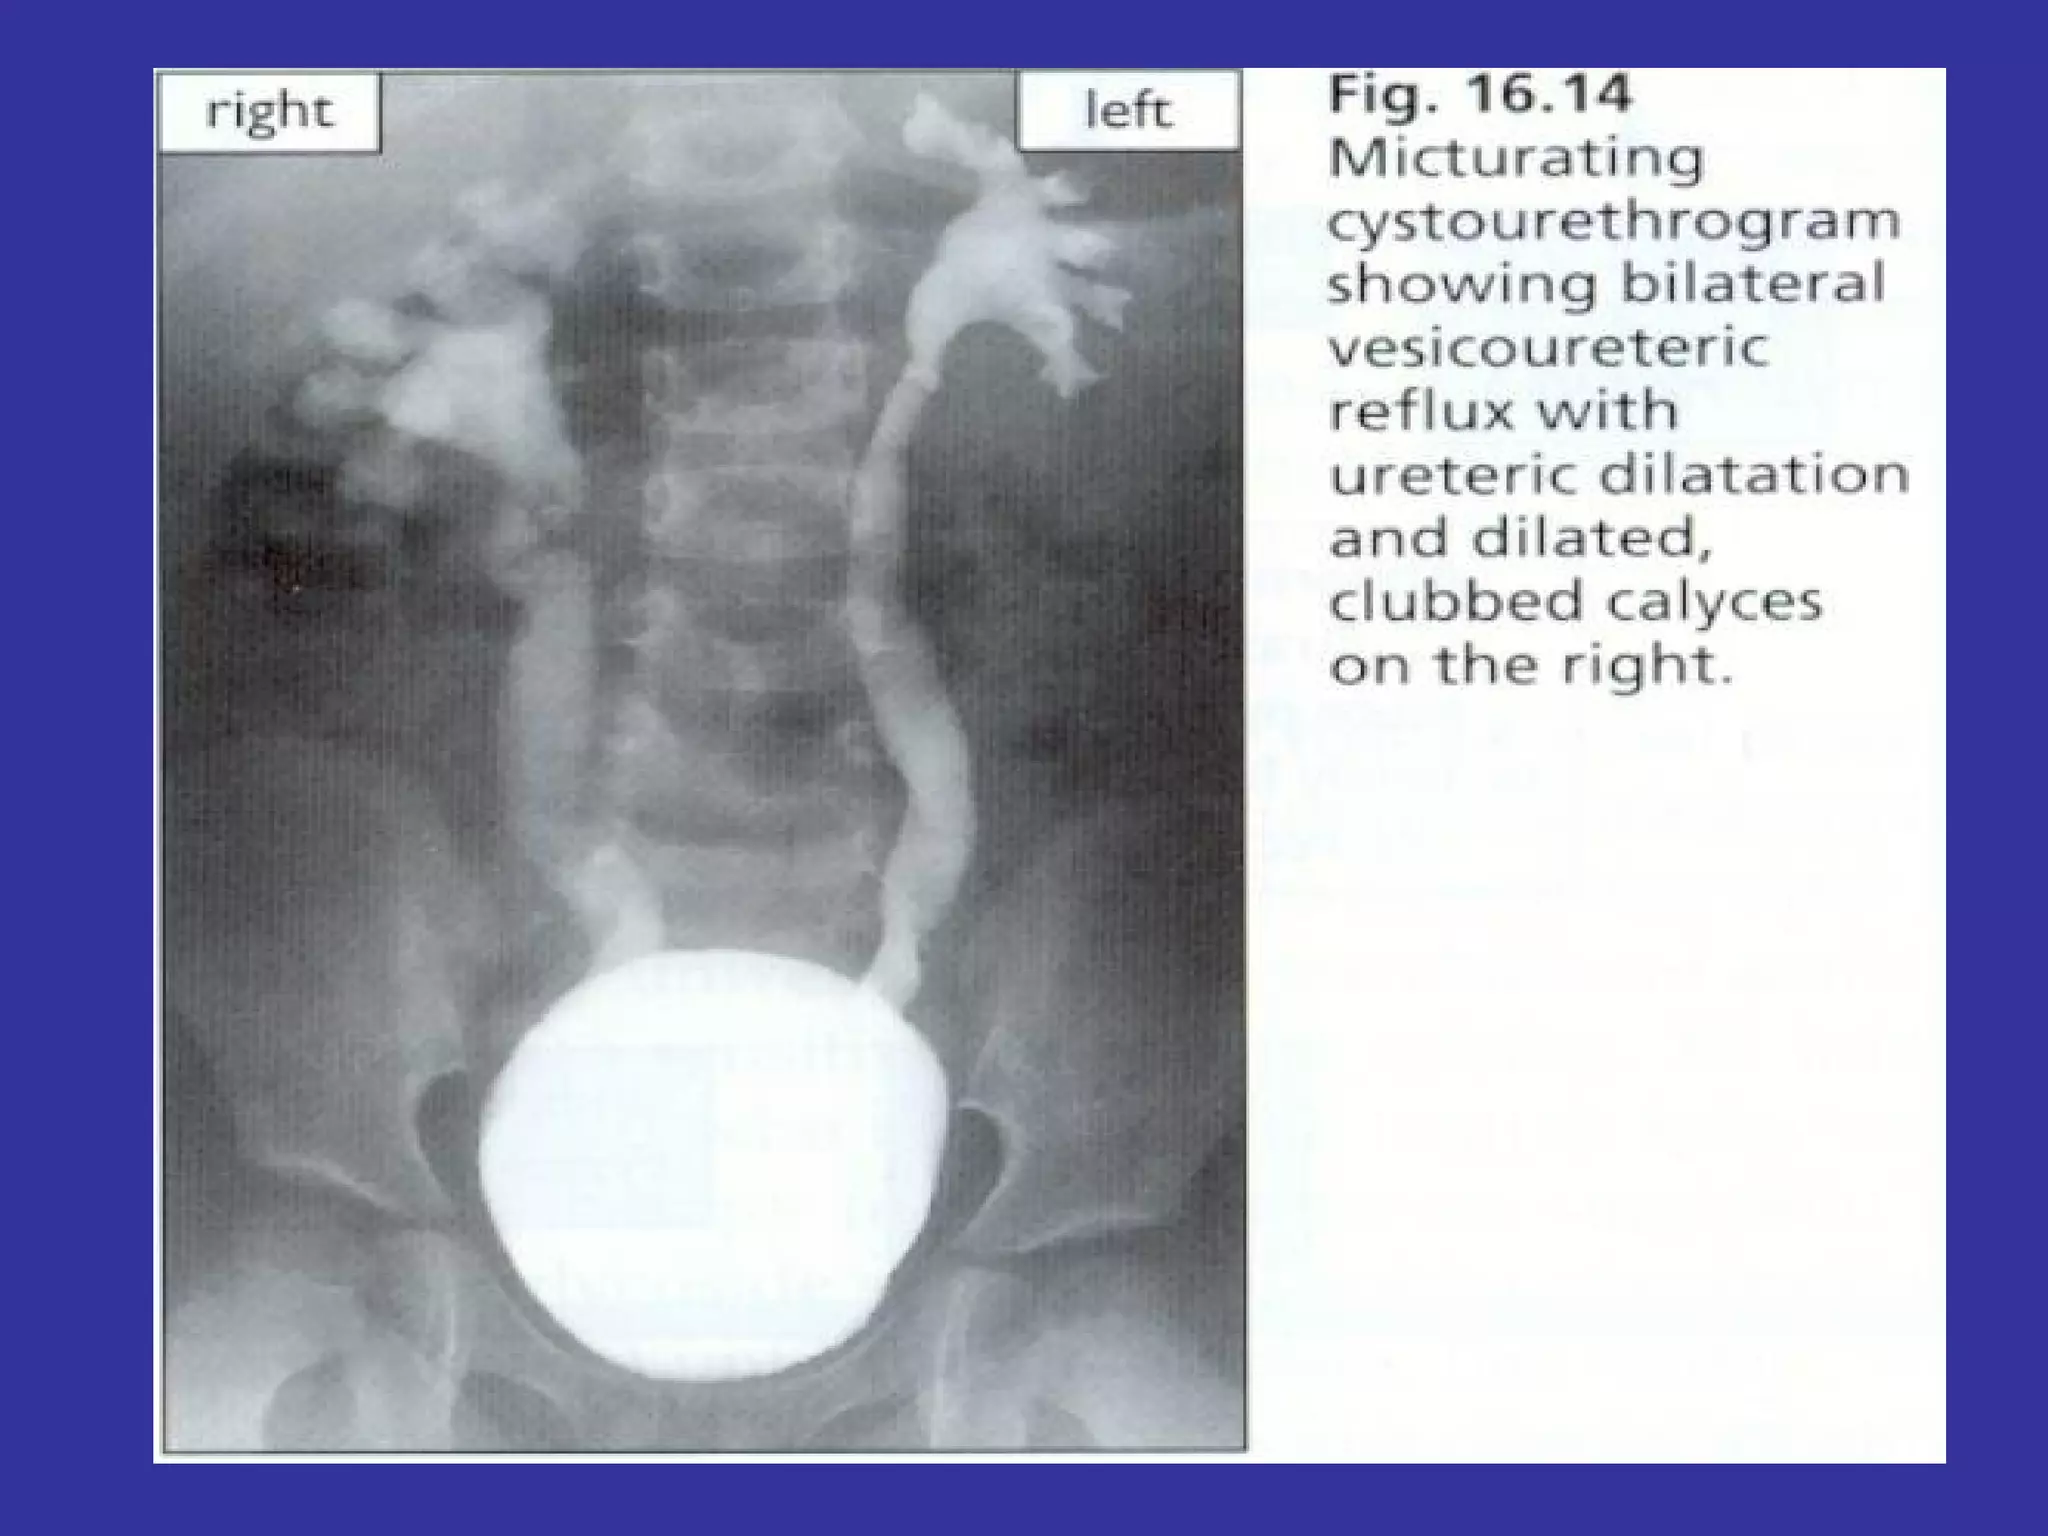

VESICO-URETHERAL REFLUX Is the passage of urine from the bladder to the renal pelvis, secondary to an incompetent  valvular mechanism at the uretero-vesical junction Epidemiology:   Family factors- 34% found to have VUR.  Classification:  REFLUX: Grade  I-   Into a non-dilated distal ureter Grade II-   Into the upper collecting system, with normal calyceal  and no dilatation Grade III-  Mildly dilated/tortuous ureter, with mild blunting of calyceal  Grade IV-  Grossly dilated ureter, moderate dilatation/tortuosity of ureter.  Grade V-   Massive reflux with gross ureteral dilatation and tortuosity of ureter S/S:   UTI sx,  HTN,  Abdominal mass secondary,  Hydronephrosis,  FTT, Enuresis LAB:   Voiding cystourethrogram (VCUG)-  Gold  standard Renal U/S- detects hydronephrosis DMSA renal scan- detects renal  scarring DMSA: Dimercaptosuccinic  acid

VESICO-URETHERAL REFLUX Isthe passage of urine from the bladder to the renal pelvis, secondary to an incompetent valvular mechanism at the uretero-vesical junction Epidemiology: Family factors- 34% found to have VUR. Classification: REFLUX: Grade I- Into a non-dilated distal ureter Grade II- Into the upper collecting system, with normal calyceal and no dilatation Grade III- Mildly dilated/tortuous ureter, with mild blunting of calyceal Grade IV- Grossly dilated ureter, moderate dilatation/tortuosity of ureter. Grade V- Massive reflux with gross ureteral dilatation and tortuosity of ureter S/S: UTI sx, HTN, Abdominal mass secondary, Hydronephrosis, FTT, Enuresis LAB: Voiding cystourethrogram (VCUG)- Gold standard Renal U/S- detects hydronephrosis DMSA renal scan- detects renal scarring DMSA: Dimercaptosuccinic acid

TX: Incidence of renal scarring, is proportional to the amount of reflux Most VUR resolves spontaneously grade I-II-III Grade IV-V unlikely to resolve spontaneously  Surgery Deflux- Dextranomer/ Hyaluronic acid copolimer injection- Resolve 88-67% of Grade I-II-III-IV ATB prophylaxis (amoxycillin-2 months) Monitor by VCUG every 12-18 months, urine cultures.

IMAGING:  *Renal U/S-   Noninvasive evaluation of structural defects.  It shows kidney size/shape, but it poorly show ureters,provides no information on function.  Diagnose urolithiasis, hydronephrosis, hydroureter, and bladder distention replacing the intravenous pyelogram (IVP) in many cases. *DMSA Renal scan:   This study frequently uses technetium Tc 99m dimercaptosuccinic acid (DMSA). Detects tubular damage and scarring and shows the kidney outline, but it does not show the collecting system. *Voiding  Cystourethrogram (VCUG):  Shows urethral and bladder anatomy and detects vesico-ureteral reflux (VUR).  Girls < 5 years with febrile UTI, or males with 2  separate UTI After first positive culture UTI:  Renal Ultrasound VCUG initially, later nuclear cystogram Renal Scan:  DMSA  (R/O scarring, even if negative VUR) Mag – 3 (obstruction)

IMAGING: *RenalU/S- Noninvasive evaluation of structural defects. It shows kidney size/shape, but it poorly show ureters,provides no information on function. Diagnose urolithiasis, hydronephrosis, hydroureter, and bladder distention replacing the intravenous pyelogram (IVP) in many cases. *DMSA Renal scan: This study frequently uses technetium Tc 99m dimercaptosuccinic acid (DMSA). Detects tubular damage and scarring and shows the kidney outline, but it does not show the collecting system. *Voiding Cystourethrogram (VCUG): Shows urethral and bladder anatomy and detects vesico-ureteral reflux (VUR). Girls < 5 years with febrile UTI, or males with 2 separate UTI After first positive culture UTI: Renal Ultrasound VCUG initially, later nuclear cystogram Renal Scan: DMSA (R/O scarring, even if negative VUR) Mag – 3 (obstruction)